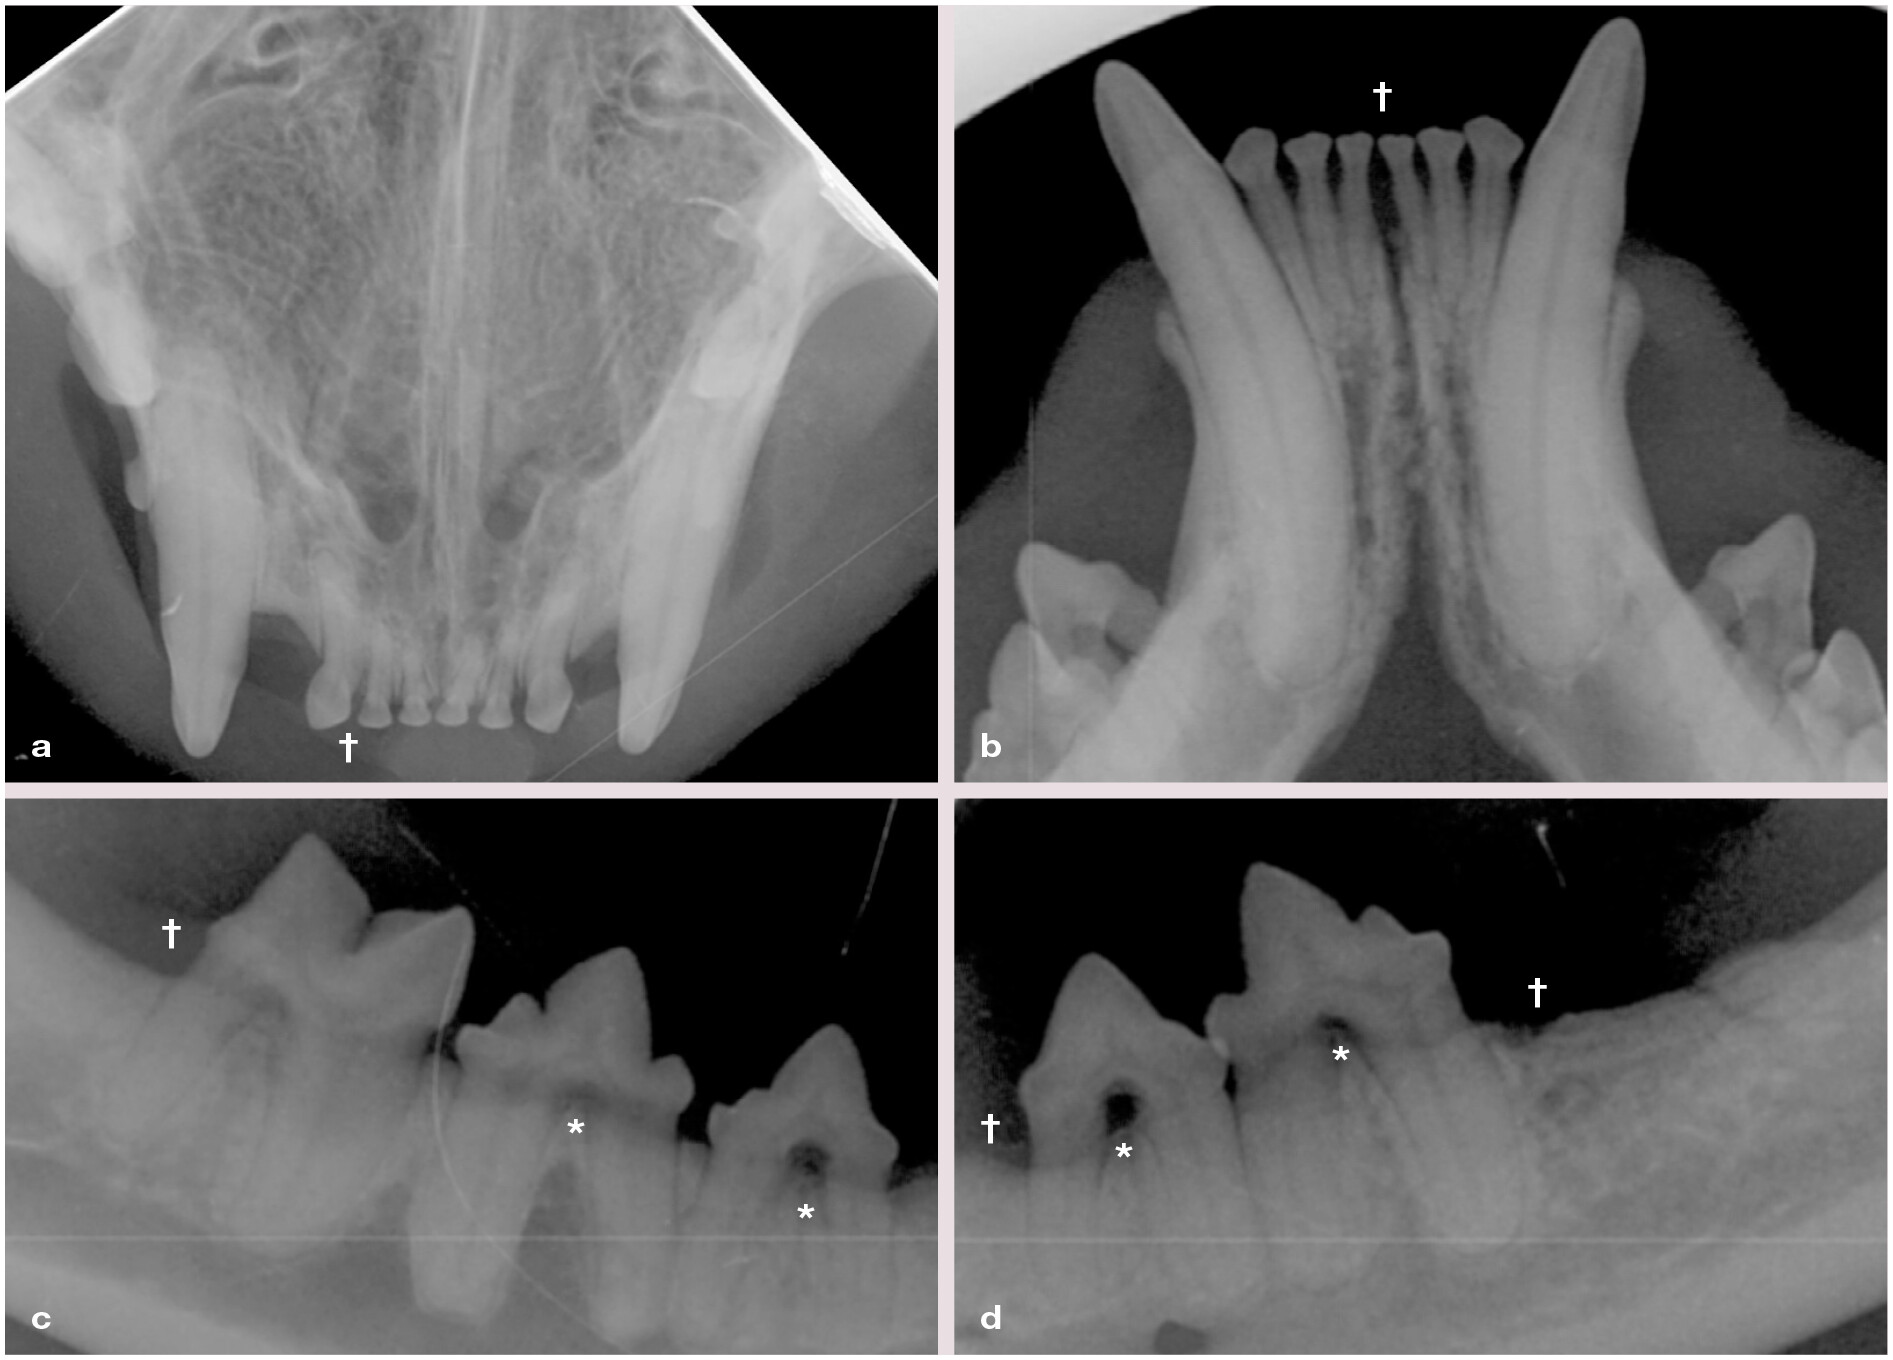

细胞因子表达与受FCGS影响的猫的疾病严重程度相关。这与人类牙周病观察到的情况相似,这并不奇怪,考虑到大多数受FCGS影响的猫同时患有牙周炎。尽管尚未完全了解FCGS患者牙龈水平的免疫宿主反应,但牙科X射线显示,FCGS与广泛且严重的牙周炎有关,外源性炎性根吸收和残留根的高发生率,表明存在高度炎症性的破坏性过程(图5)。这种反应也可能反映了口腔黏膜慢性炎症引起的细胞因子积聚,这些细胞因子在不同病因引起的慢性炎症中似乎几乎没有变化。

图5:一只5岁的家猫,临床和组织病理学上证实患有猫口腔慢性炎症(FCGS)的短毛猫。

(a) 上颌切牙的咬合面视图。 (b) 下颌切牙的咬合面视图。© 右下颌PM3至M1。 (d)左下颌PM3和PM4。放射照片显示受影响牙齿的根分叉处有轻度至中度的半普遍性水平牙槽骨丧失(†)和I型牙齿吸收(*),以及左下颌第一磨牙缺失和下颌尖牙的颊侧骨扩张。